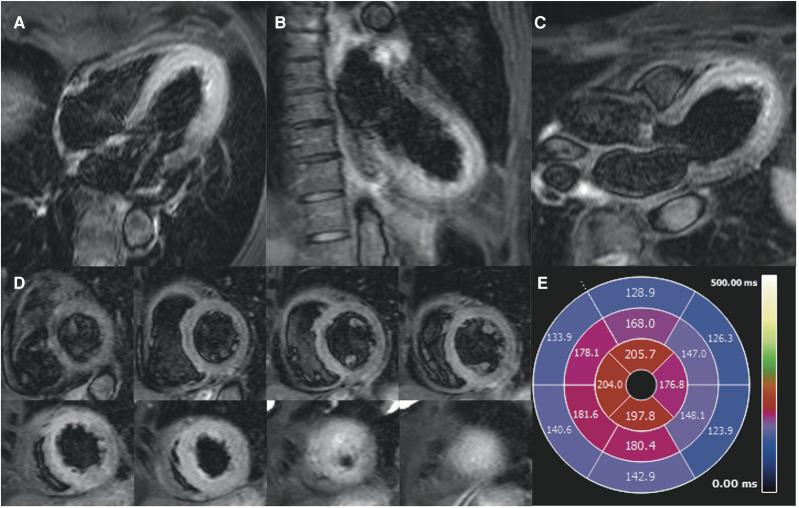

A 69-year-old lady was admitted with chest pain and shortness of breath. She was found to have classical TTS with the characteristic wall motion abnormalities on echocardiogram, left ventricular angiogram, and CMR. Her CMR also demonstrated strongly positive myocardial T/T mapping that matched the wall motion abnormalities and the less frequently described positive early and late gadolinium enhancement.

一名69岁女性因胸痛和气短入院。经超声心动图、左心室血管造影和CMR检查,发现她患有典型的TTS,伴有特征性的室壁运动异常。她的CMR检查还显示心肌T/T映射呈强阳性,与室壁运动异常相符,且有较少被描述的早期和延迟钆增强阳性表现。